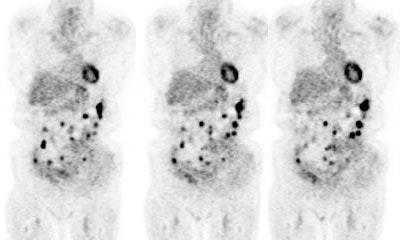

Recurrent colorectal cancer: The patient shown below had a history of colon cancer and was being evaluated for two pulmonary nodules that were suspected to be metastases. The FDG PET demonstrated uptake in the pulmonary nodules (not shown) and also revealed diffuse omental metastases. (Click image to view avi file 1.5 MB) |

|